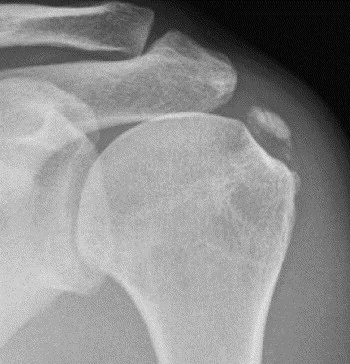

De klassieke radiografie en echografie zijn de beste basisonderzoeken voor deze pathologie. Dit laat toe om een classificatie uit te voeren van deze calcificatie die vooral belang heeft in het voorspellen van het verloop (de prognose).

Als de calcificatie wazig en brokkelig voorkomt, is ze meestal vrijgekomen in de slijmbeurs. Dan treedt er resorptie op. Opeenvolgende radiografieën kunnen de evolutie van het calciumdepot aantonen.